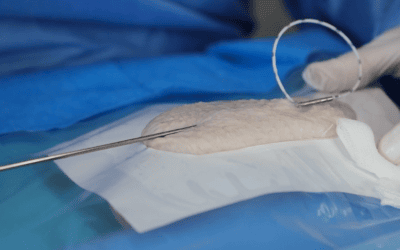

Conocer el comportamiento del ultrasonido en función de los tejidos atravesados es especialmente útil para evitar posibles errores de interpretación de la imagen y una mala elección del lugar de punción. Permite entender mejor qué está pasando en el momento del mapeo vascular pero también durante la inserción de la aguja en vena, lo cual conlleva a una mejor prevención del fracaso de colocación del acceso vascular.